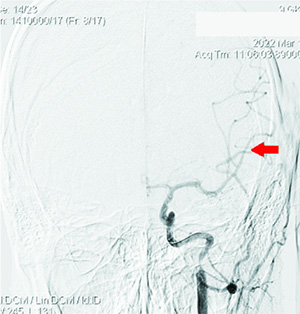

При выполнении КТ-ангиографии головного мозга выявлена окклюзия левой ВСА до М1-сегмента (см. рис. 1).

Проведена диагностика: определялась окклюзия несколько дистальнее устья ВСА слева, коллатеральное заполнение сосудов левой гемисферы из правой ВСА и позвоночных артерий, локальная окклюзия ветвей первого порядка левой СМА после бифуркации (см. рис. 2 и 3).